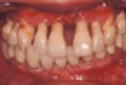

♦歯周炎

歯肉の形態:歯と接している歯肉がさらにぶよぶよと腫                    れ、退縮する。

ブラッシングで出血や膿がでる。

歯と歯の間が広がり、食べ物もよく詰まる。

歯肉が退縮して、歯が長く見える。

炎症はさらに進み、ポケットは深くなり 深部の歯垢中の細菌は毒性が強く骨(歯槽骨)を破壊し、溶かします。